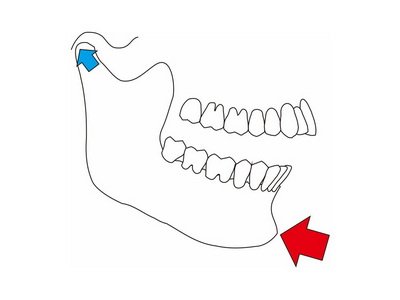

Dawson法は下顎頭を関節窩の前上方に誘導する (図1)

(図1)Dowson法